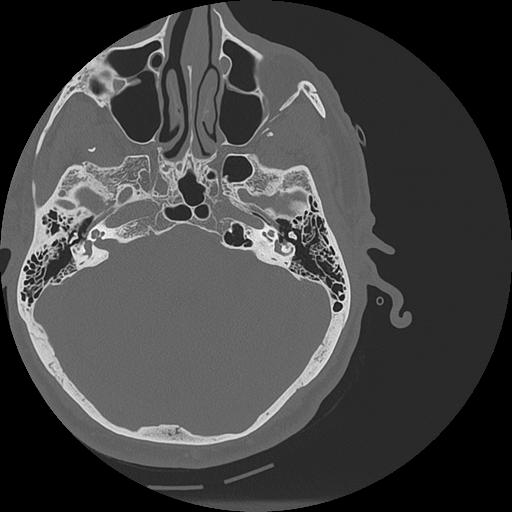

7 HUESO,,Vol,0.5,HUESO,,